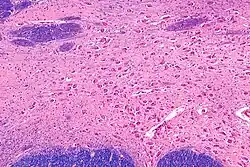

![]() Intermediate magnification micrograph of the nucleus basalis. LFB-HE stain. | |

In the human brain, the nucleus basalis, also known as the nucleus basalis of Meynert or nucleus basalis magnocellularis, is a group of neurons located mainly in the substantia innominata of the basal forebrain.[1] Most neurons of the nucleus basalis are rich in the neurotransmitter acetylcholine, and they have widespread projections to the neocortex and other brain structures.[2]

The nucleus basalis in humans is a somewhat diffuse collection of large cholinergic neurons in the basal forebrain.[2] The main body of the nucleus basalis lies inferior to the anterior commissure and the globus pallidus, and lateral to the anterior hypothalamus in an area known as the substantia innominata.[1] Rostrally, the nucleus basalis is continuous with the cholinergic neurons of the nucleus of the diagonal band of Broca.[1] The nucleus basalis is thought to consist of several subdivisions based on the location of the cells and their projections to other brain regions.[2] Occasional neurons belonging to the nucleus basalis can be found in nearby locations such as the internal laminae of the globus pallidus and the genu of the internal capsule.[1]

Neurons of the nucleus basalis are particularly vulnerable in age-related neurodegenerative diseases such as Alzheimer's disease,[3] Parkinson's disease, and several others.[2] The resulting decrease in acetylcholine in the brain is thought to contribute to the decline in mental function of affected patients.[3][2] For this reason, most currently available pharmacological treatments for dementia focus on compensating for faltering function of the nucleus basalis through artificially increasing acetylcholine levels. Because many other systems also are compromised in neurodegenerative diseases, the benefits of selectively increasing cholinergic function are limited.[12]